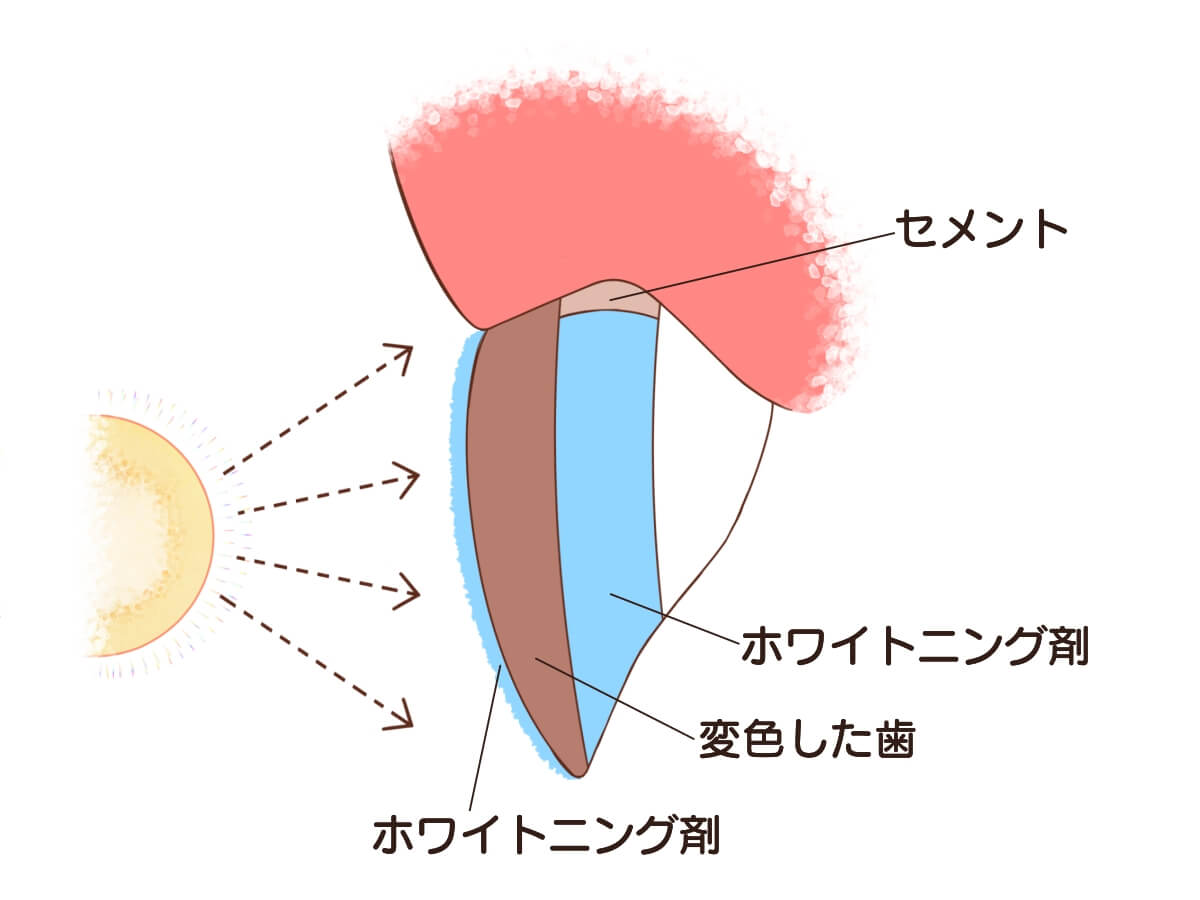

ウォーキングブリーチ法

歯の内部にお薬を封入して白くする方法です。

パワーブリーチ法

神経がない歯を白くするオフィスホワイトニング。歯に負担がかからずに白くすることができます。

効果が高いホワイトニングと組み合わせることで1回で白くすることも可能です。

・ウォーキングブリーチと異なり、歯の根や骨に影響がありません。

・神経がない歯でも白くすることができます。

・他の効果の高いホワイトニングと併用して行うことができます。

パワーブリーチのデメリット

・単独でパワーブリーチを行う場合は、回数がかかってしまう場合があります。

・神経がある歯や神経の治療が不完全な歯などはできません。

・パワーブリーチを行う歯の裏側に矯正後の固定式のリテーナーが付いている場合はパワーブリーチができません。